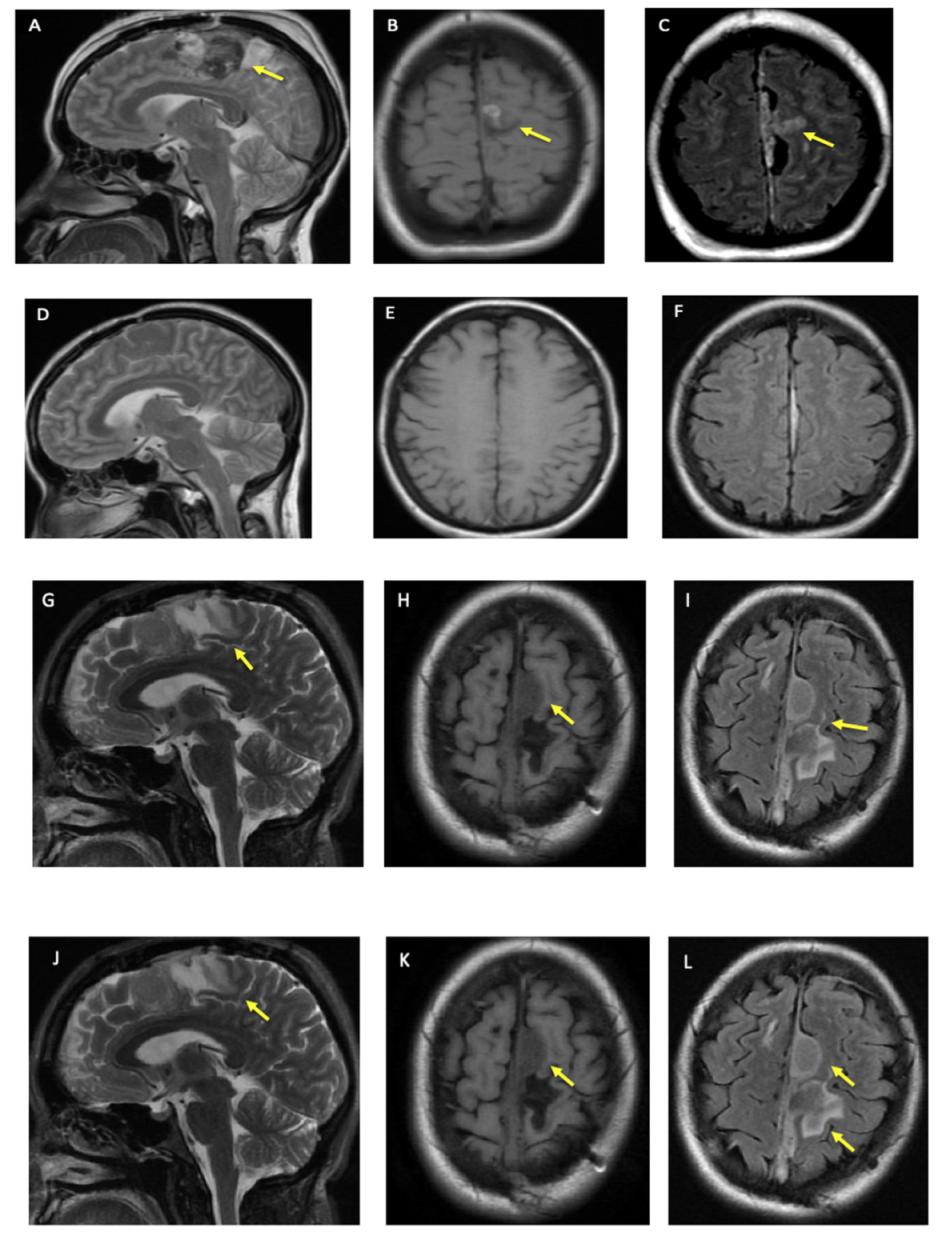

Figure 1.

Patient’s Brain MRI. (A–C) show brain MRI at the time of initial presentation in 2013, (A) is T2, (B) is T1 FLAIR, and (C) is T2 FLAIR. (D–F) is brain MRI 3 months after the patient’s initial craniotomy. (D) is T2, (E) is T1 FLAIR, and (F) is T2 FLAIR. (G–I) is 7 years after initial MRI, (after the patient was on cobimetinib for 6 months). (G) is T2, (H) is T1 FLAIR, and (I) is T2 FLAIR. (J–L) are 8 years after initial MRI, (on cobimetinib for 13 months). (J) is T2, (K) is T1 FLAIR and (L) is T2 FLAIR. Single yellow arrows in different figures shows the lesion after biopsy and debulking. In (L), anterior and first arrow is highlighting meningioma in addition to lesion as denoted by 2nd and posterior arrow.

In 2020, the patient started cobimetinib, and has not had any progression in clinical and imaging findings (Figure 1G–L). In addition, there are no clinical or radiographic findings to suggest other system involvement over the last eight years.